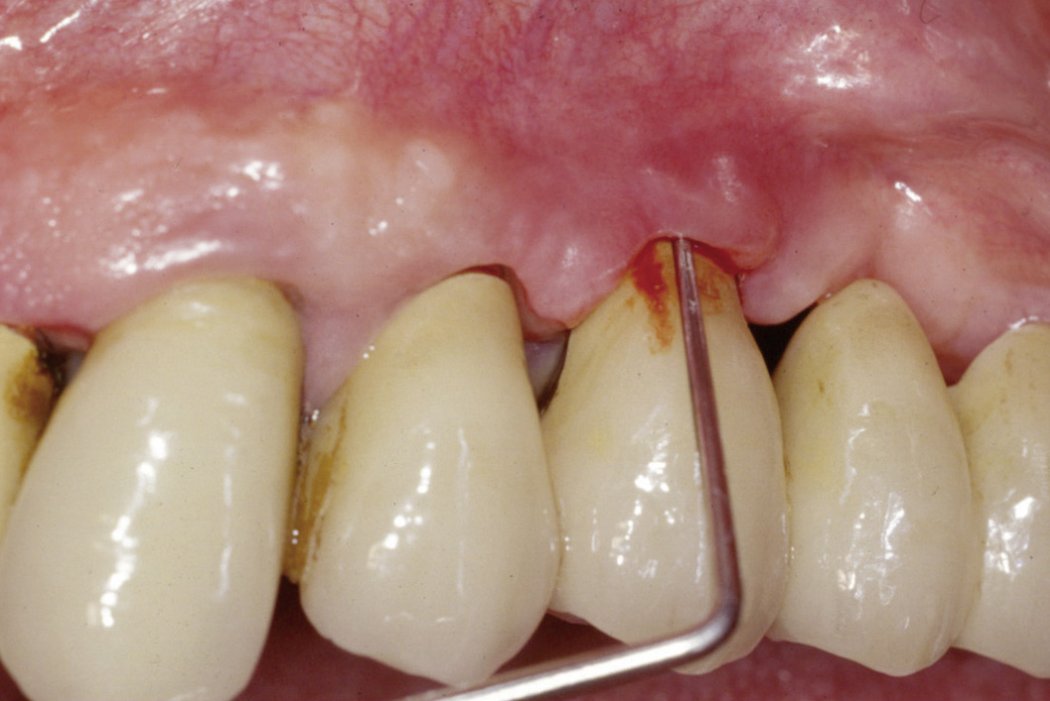

Peri-implant infections are pathological conditions surrounding dental implants. Mucositis refers to inflammation and ulceration in the soft tissues around an implant and is a reversible host response to periodontal pathogens. Peri-Implantitis, the destructive inflammatory process affecting both soft and hard tissue surrounding a dental implant, is more severe and leads to bone loss1.

The typical signs and symptoms of the diseases, as discussed in various consensus conferences, can be described as follows2-8:

Mucositis

Peri-implantitis

A reliable diagnosis of peri-implantitis requires the simultaneous presence of all above listed signs and symptoms. A single feature alone is not sufficient for the diagnosis.